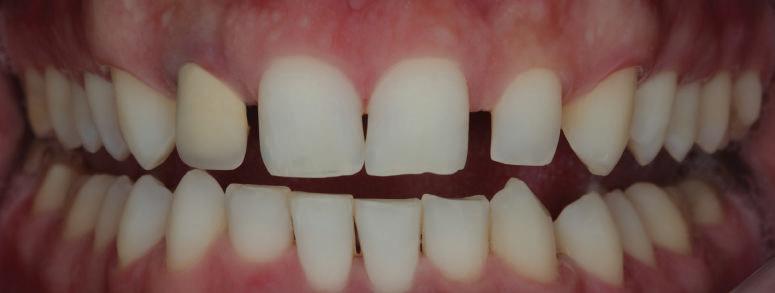

Пациентът постъпи в клиниката с молба за тотална рехабилитация на усмивката. Той не харесваше централ ните си резци, които според него бяха твърде къси и квадратни. Имаше раз стояние от медиално и дистално на латералните му резци. Друго сериоз но оплакване бе свързано с металоке рамичната корона на зъб 12, която бе жълтеникава и неестетична, като цяло не харесваше вида на венците си и както самият той се изразяваше, „вижда се прекалено много от венците при усмивка“.

След диагностиката бяха направени екстра- и интраорални снимки, както и рентгенографии; професионалното почистване бе от изключителна важ ност, бяха дадени и инструкции за лич на орална хигиена. Бе направено интра орално сканиране с Medit i500. Цялата тази информация бе използ вана в приложението Smilecloud за 2D биометричен дизайн. В приложението са налични естест вени форми на зъбите и щом бяха под брани зъби и бе направен дизайн

библиотеката на Exocad. Струва си да се отбележи, че 2D дизайнът от Smile Cloud бе спазен до последния детайл в Exocad smile creator с цел да се създаде 3D obj файл със зъбните форми. След като естетичният дизайн бе готов в model creator модула на Exocad, адитивен 3D мок-ъп модел бе експорти ран и принтиран от принтер Formlabs 3. Моделът бе използван за направата на силиконов водач, за да се изготви мо тивационен мок-ъп в устата на паци ента и да се оценят естетичните па раметри. След като пациентът одобри вида на усмивката си, мок-ъпът бе използван за финализиране дизайна на усмивка та. Мок-ъпът бе използван също така като водач по време на мекотъканна та хирургия, както и при препарация на зъбите.

Препарираните зъби бяха импорти рани в Exocad и насложени върху ес тествените форми от биометричния дизайн, като така стана ясно дали зъ бите са били препарирани коректно. По този начин зъболекарят и зъботехни кът работят в една и съща екосистема и резултатът е оптимален. С короната се справихме чрез диги тална редукция на циркония в Exocad, като по този начин на практика създа дохме циркониево кепе, след което про изведохме фасета от IPS Empress Cad Multi. Кепето от Katana Zirconia на зъб 12 с букално послойно нанесена керами ка бе фрезовано (послойното нанасяне бе направено, за да се подобри връзката и да се осигури адхезивно циментиране на фасетата към циркониевото кепе, както и за да се напасне цветът към този на съседните зъби). При първото сканиране регистрирах ме цялата горна зъбна дъга, така че, ко гато се наложи да сканираме повторно, бе изтрит и сканиран наново само зъб 12, тъй като венците не бяха отдръп нати при второто сканиране.

Една седмица след препарацията на зъбите и циментирането на цирко ниевото кепе бяха изработени 12 IPS Empress Cad Multi фасети. Макро- и микротекстурата на фасе тите бяха направени на ръка, след кое то бяха нанесени 3D характеризации с боички, а полирането отново бе напра вено ръчно, за да им се придаде естест вен и естетичен вид. Предизвикателството тук беше короната да има същите оптични характеристики като тези на остана лите зъби при естествена светлина, през поляризационен и флуоресцентен филтър. 3D принтерът бе Fromlabs, софтуерът за фрезоване – Mill Box, а фрез апаратът –imes icore CORiTEC 350i. В крайна сметка постигнахме ес тествен вид на усмивката с натурал на зъбна морфология при изцяло диги тален протокол, при който дизайнът бе направен първоначално и през всич ки етапи на лечението се придържахме към него до самия край Излишно е да отбелязваме, че всички сме удовлетворени от постигнатото! Преди След Победител в категория „Клиничен случай с изцяло дигитален протокол“ в конкурса „Усмивка на годината 2022“